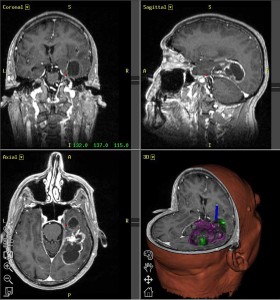

Glioblastoma: scoperta proteina che lo rende così resistente

Un altro piccolo passo avanti per riuscire a capire meglio come cresce e resiste alle terapie il più letale e aggressivo tumore del cervello, il glioblastoma, di cui si contano circa 1200 nuovi casi ogni anno in Italia e per il quale purtroppo ancora non esistono terapie efficaci.